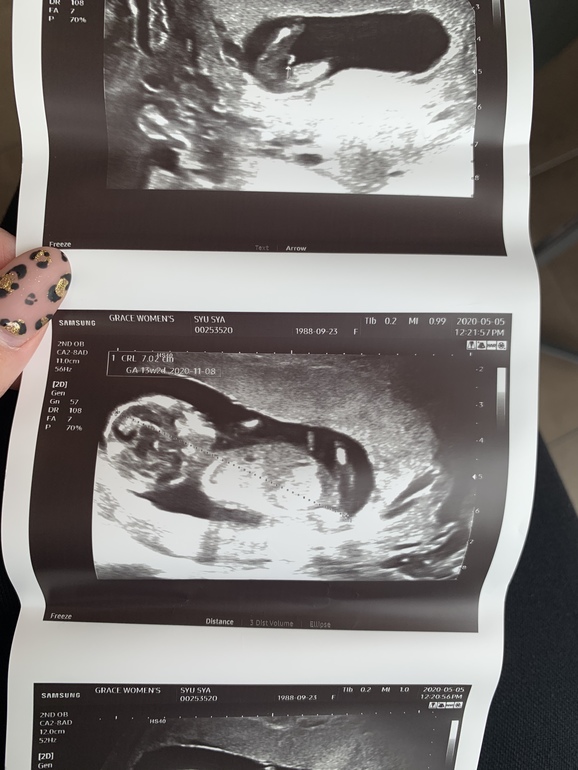

До 11 недель ходили в одну клинику, а сейчас решили поменять. Пришли на УЗИ, и врач очень уверено говорит, что мальчик. Даже фото показал🙈😅 Вот теперь думаю, насколько это точно.